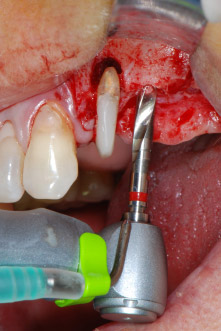

Имплантологичното ложе е подготвено в позиции 25 и 26 с ротиращи инструменти, използвайки обратен наконечник 20:1 с усъвършенстван и мощен имплантологичен мотор (Implantmed, W&H) (Фиг. 8).

Имплантологичното ложе е обработено с новия имплантологичен мотор (Фиг. 20), в комбинация с обратен наконечник, специално проектиран за орална хирургия и имплантология.

Предавателното съотношение20:1 заедно с високия въртящ момент до 6.2 Ncm осигуряват препарация на ниски обороти, поставяне на имплант и рязане. Финалната препарация близо до мембраната на синуса отново е извършена с пиезоелектрически апарат и накрайник със сферичен диамантен връх.